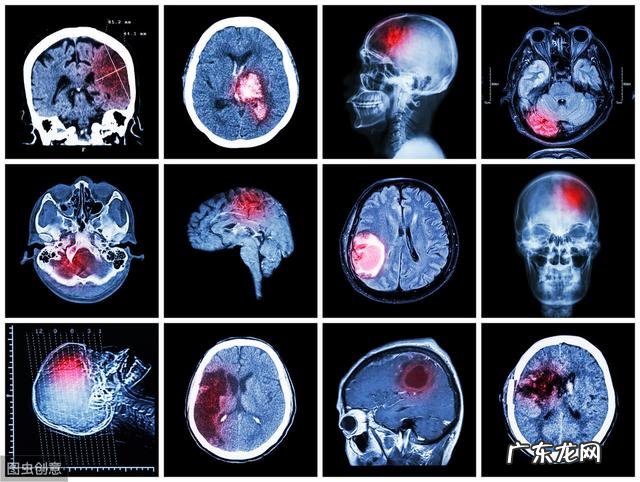

为什么高血压容易引起脑出血高血压脑出血是由于脑内小动脉硬化,玻璃样变,形成微动脉瘤,加之脑内动脉外膜不发达,缺乏外弹力层,中层肌细胞管壁较薄,在用力、情绪激动等因素引起血压骤然升高时可造成动脉血管破裂出血 。由于出血后形成血肿压迫局部致脑内占位性病变,破裂血管不再出血而闭塞 。

高血压脑出血急性期,由于血肿的占位效应,血管通透性增加,细胞毒效应及血肿挤压或血块阻塞脑室所致脑积水等综合因素,最终产生颅内压升高 。若颅内压升高进一步发展会形成脑疝,脑疝的形成又加重脑水肿和颅内高压,引起严重的复杂的临床征象 。脑出血急性期的zhi疗原则:保持安静,防止继续出血,积极zhi疗脑水肿,降低颅内压,调整血压,改善循环,加强护理,防zhi并发症 。

脑出血急性期,脑实质突然出现明显占位的血肿,造成脑室受压,中线结构移位 。同时,颅内压急剧增高,致使以原有的血压水平难使血流进入颅内,颅内血流量减少,血压中枢受缺血的刺激而反射性地升高血压,以克服增高的颅内压,维持和保证适当的脑灌注压 。